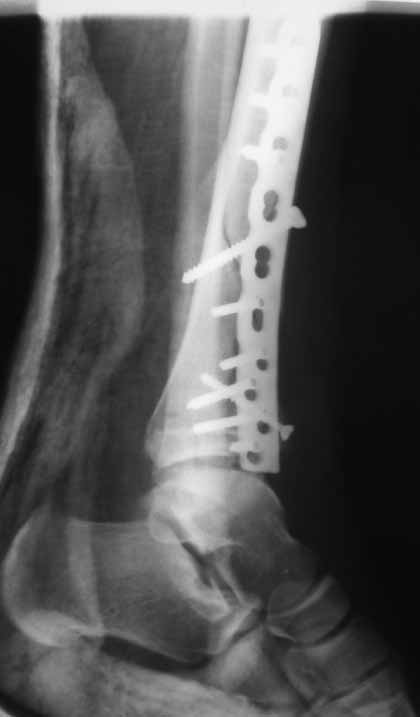

Отчет по "пилону":)))

Извиняюсь пропал - оперировал "пилон". В форуме не хотел обсуждать финансовые возможности пациента. Потянул комбинированную пластину. Опыт общение с пластиной "крест" есть - не очень понравилось - слишком много места занимает, даже с учетом обрезаний лишнего. Сделал доступ огибающий медиальную лодыжку спереди. В переднем крае оказался достаточно крупный отломок - удалось зафиксировать винтом. Дефекта кости не оказалось.

Какой таран? в одном сегменте повреждается одно или другое. Крайне редко обе части. Анатомическая репозиция безукоризненна,но для чего межфрагментарный винт при использовании LCP это очевидное нарушение методики. А по поводу Мальтийского креста, то это оличный незаменимый, в ряде случаев, фиксатор, но не для этого перелома, абсолютно!С Уваением! Сергей.